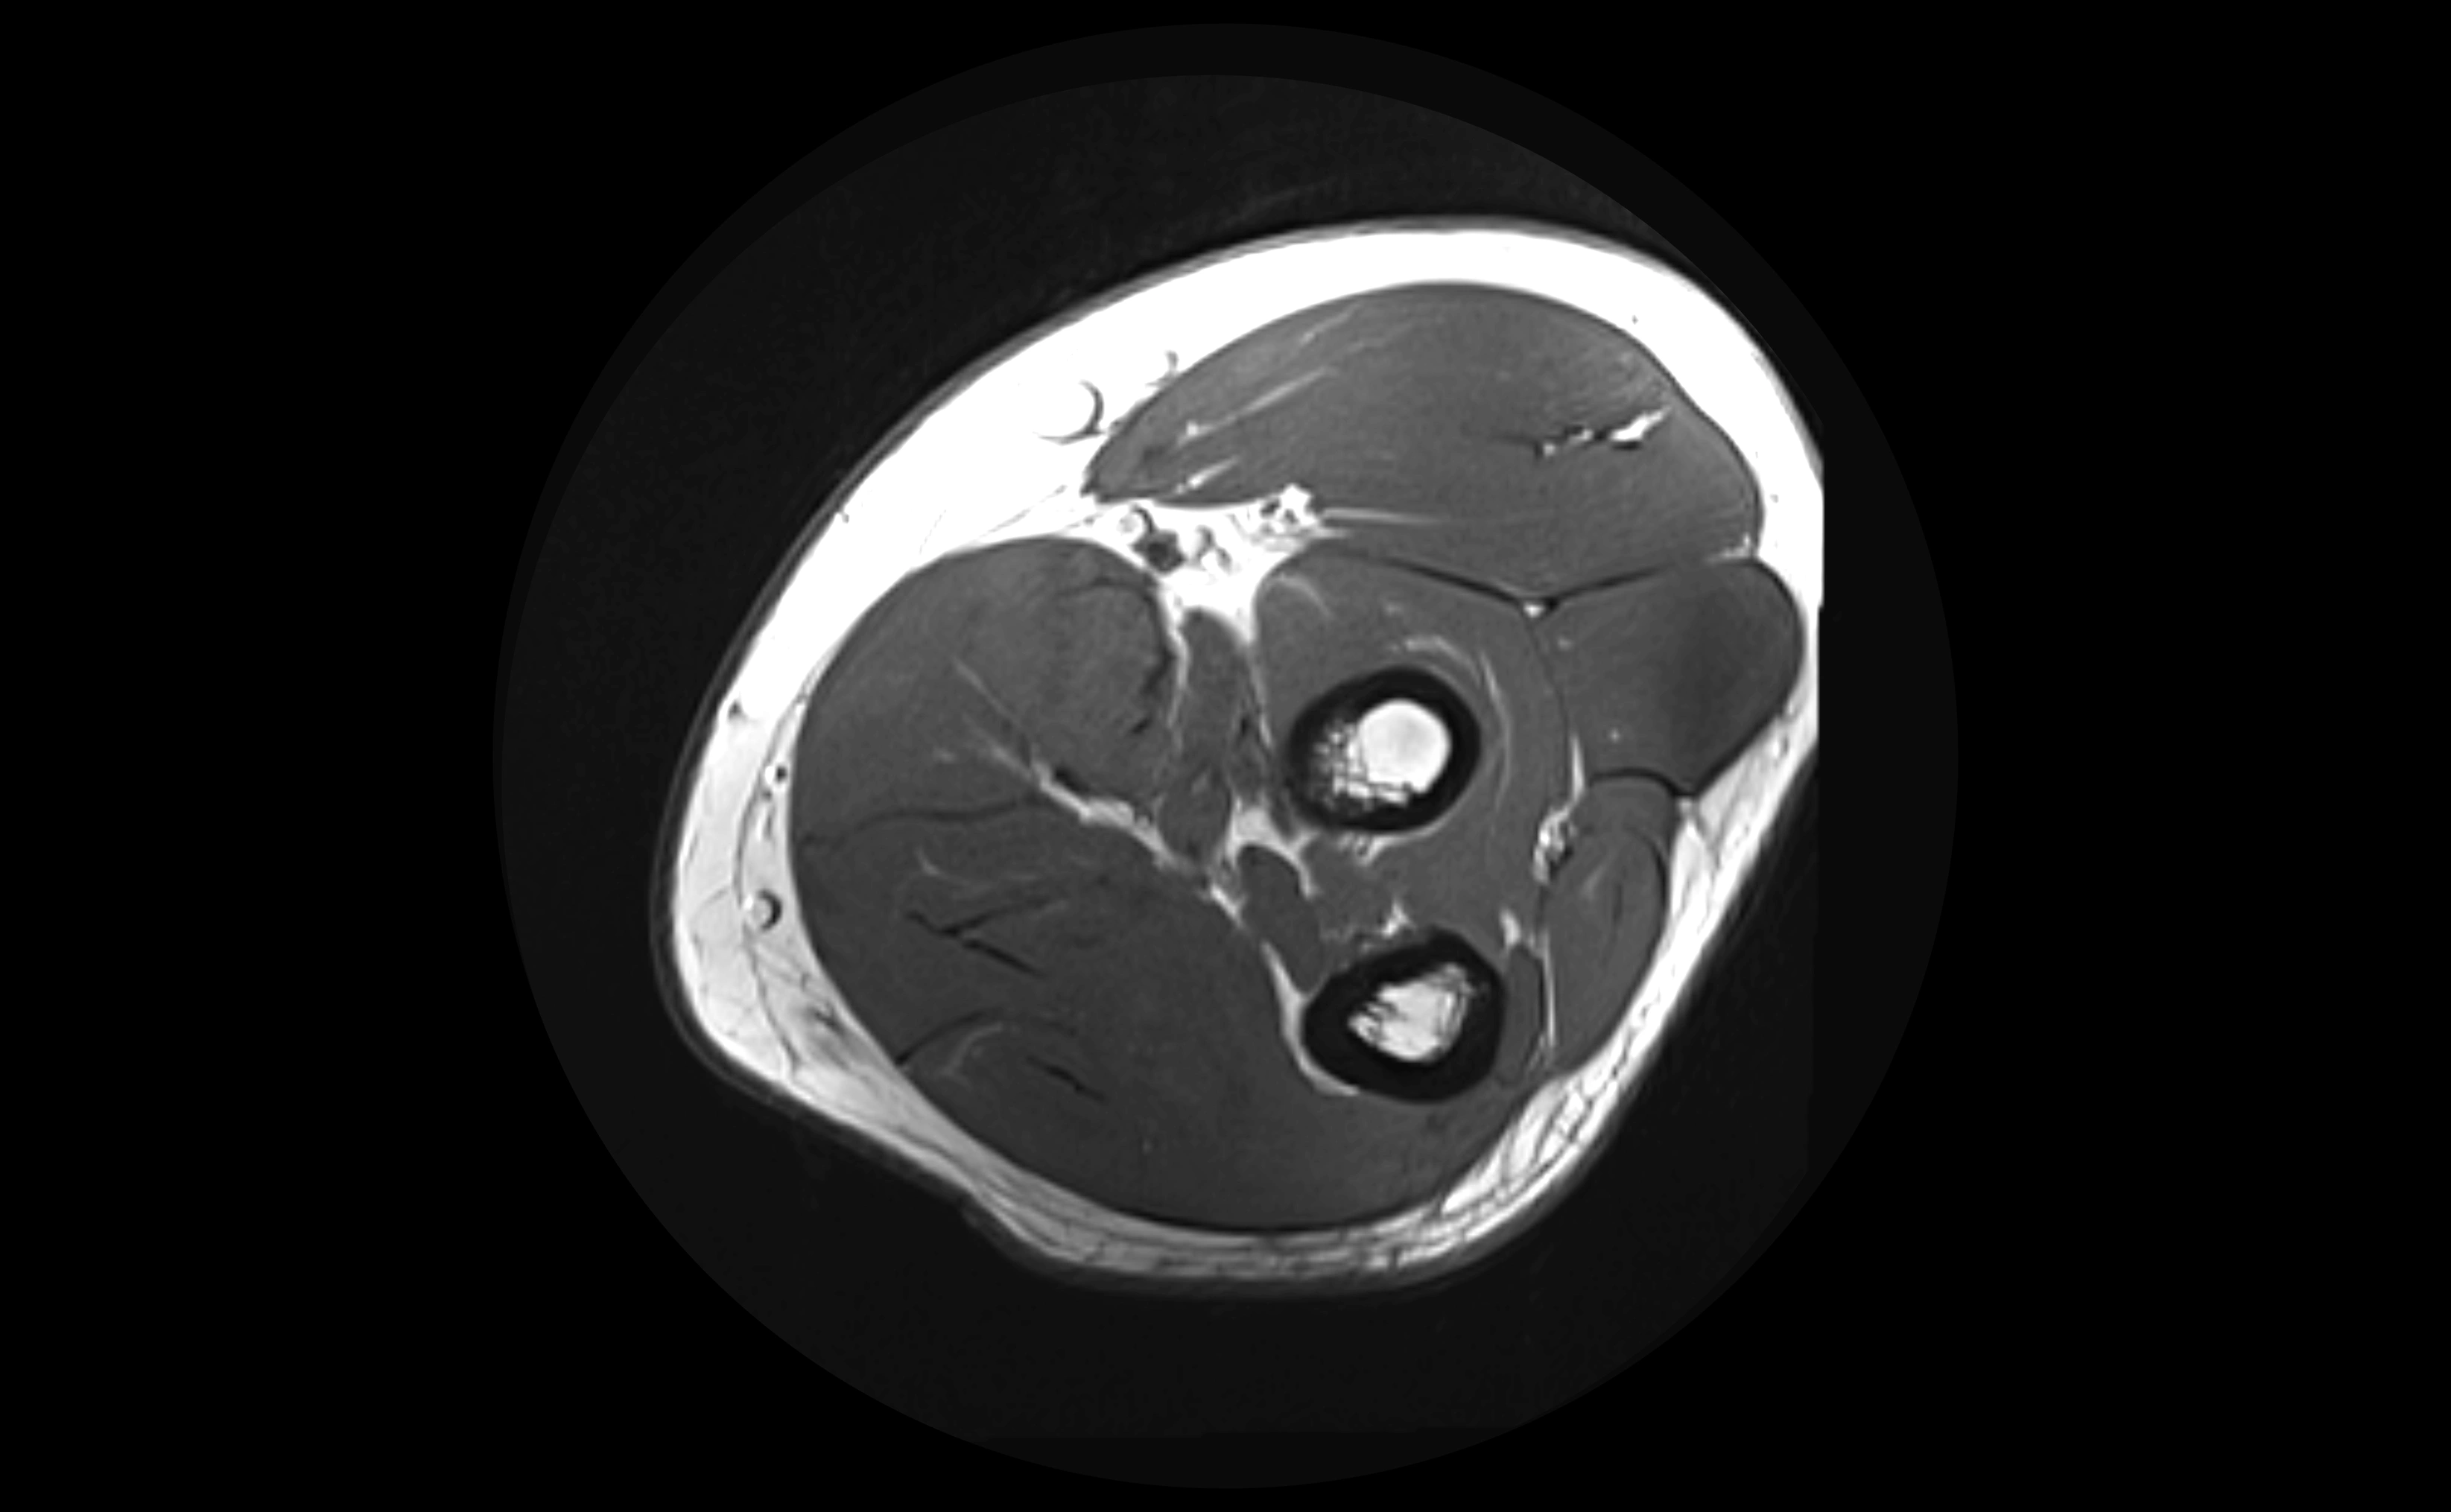

MRI Appearance

T1-weighted images:

• Ligament: low signal intensity (dark), appearing as a continuous band around the radial head.

• Adjacent fat and marrow: bright, creating contrast with the ligament.

T2-weighted images:

• Ligament: low signal (dark) with clear delineation from joint fluid.

• Fluid or edema: bright hyperintense, separating or surrounding the ligament in partial tears.

• Complete tear: discontinuity or non-visualization of ligament fibers, often with joint effusion.